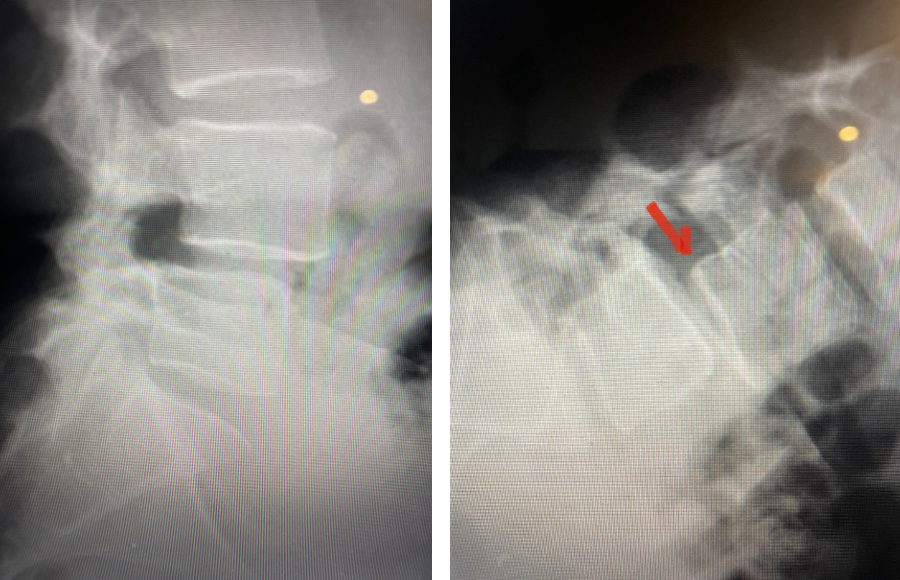

This 42-year-old female presented after complaining of low back pain with intermittent pain going down her left leg and numbness of her feet. She reported having a fall on her back about ten years ago and since then has had back pain. On exam, she had ⅘ weakness of her left dorsiflexion and extensor hallucis longus weakness. MRI revealed a “garden variety” L4-5 grade 1 spondylolisthesis with stenosis, although it was read as having a left pedicle “stress reaction” and suspicion of bilateral spondylotic defects. This was an interesting reading of the MRI, as it is uncommon to have spondylotic defects at L4 which occurs 5-15% versus at L5 which occurs in 85-95% of cases. Most people have an L5-S1 spondylolisthesis with an L5 pars defect. There was thickened ligamentum flavum worse on the left adjacent to the facet with concentric stenosis and bilateral foraminal stenosis. She had tried physical therapy and epidural injections, which did not help. She had trouble standing for long periods of time. Neurologically, she was intact.

Fig 1: Plain X-rays demonstrating a grade 1 L45 spondylolisthesis with dynamic translation of approximately 4 mm (arrow).

Plain lumbar x-rays were done with flexion/extension views. Surprisingly the patient had 4 mm of anterior translation and slight angulation in flexion (Fig 1). This was unexpected because in degenerative spondylolisthesis the patient more commonly has auto stabilized by formation of stabilizing arthritic structures and has no motion on dynamic x-rays. However, approximately 20% of patients will have some degree of translation on flexion-extension x-rays with degenerative L4-5 spondylolisthesis. Because she had failed all means of conservative management, it was felt that the patient would benefit by a lumbar decompression and instrumented fusion because of the acute instability demonstrated on x-rays and her age.